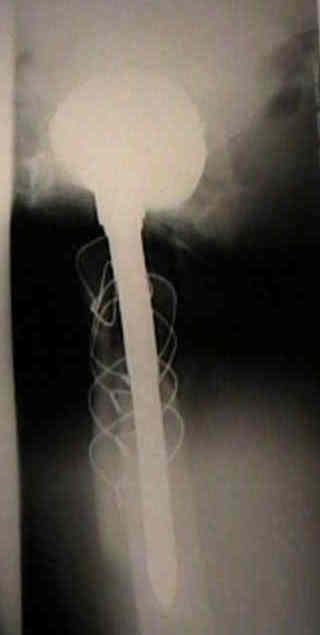

Loosening of Press Fit Acetabular Components

(press fit acetabular components)

normal bone ingrowth

- generally for bone ingrowth to occur, the component must lie with 50 micrometers of the acetabulum, inorder for host bone ingrowth to occur;

- as noted by Bloebaum RD, et al (1997), bone ingrowth into component averages only 12%, even though 84% of the cup surface was in contact w/ periprosthetic bone;

- bone ingrowth was found to be uniform in all zones, most likely due to the uniform distribution of stresses from the metal backing;

Effect of Femoral Head Size

- higher frequency of isolated acetabular loosening was associated with use of a 32-mm femoral head.

- increased loosening rate of acetabulum w/ larger femoral head diameter may reflect thinner poly and higher frictional torsional stresses transmitted to the acetabular component;

- w/ smaller femoral heads, the frictional forces are less and the polyethylene is thicker